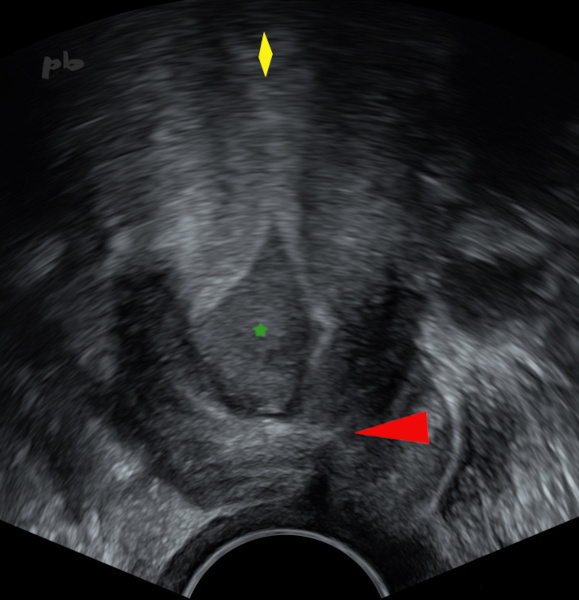

4 – Hématométrie – Sténose de l’orifice externe (OE)

(même patiente que 3)

Echographie endovaginale.

Rétention hématique. Hématocolpos avec un canal cervical très élargi (★) en lien avec une sténose de l’OE du col (►).Corps utérin (♦)